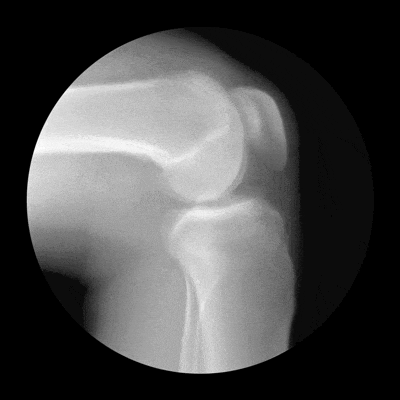

陈东峰介绍,骨关节炎是老年人的高发疾病,主要表现以关节软骨的磨损和破坏。随着年龄增长,关节软骨逐渐退化,软骨细胞合成功能下降,加上长期重复使用和负荷,关节边缘代偿性增生,导致软骨变薄、表面粗糙甚至碎裂。